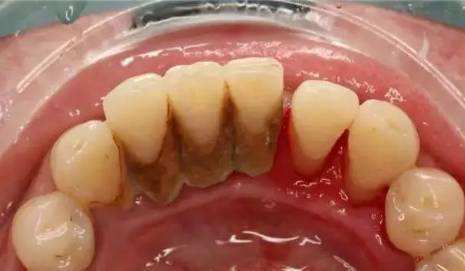

牙菌斑与唾液中钙磷离子结合钙化成牙石。就像贝壳上的钙化物一样,刷牙只是简单的清洁,牙石依然会形成。只是不同的牙齿,牙石多少会有所差异!

简单来说,口水中的矿物质+软细菌=牙石(硬细菌)

牙石不清理,这些“硬细菌”会慢慢吞噬你的牙龈,牙齿也会越来越松动甚至脱落,还会有口臭、刷牙出血等症状,牙石被清理掉,牙齿只是露出了本来的样子而已。

超声波洗牙,是通过超声波的高频震荡作用去除牙石、菌斑和色素清洁牙面,以延迟菌斑和牙石的再沉积;其具有高效、优质、省时省力的特点,对牙面的损害极小。

超声波洗牙就是通过超声波的高频震荡作用,去除牙齿上的牙结石、烟渍和茶斑,可以防止牙龈出血或者牙齿松动的情况,帮助治疗牙周炎等口腔疾病,而且对牙面的损害非常小,洗牙的时间也很短,治疗方便,效果明显。